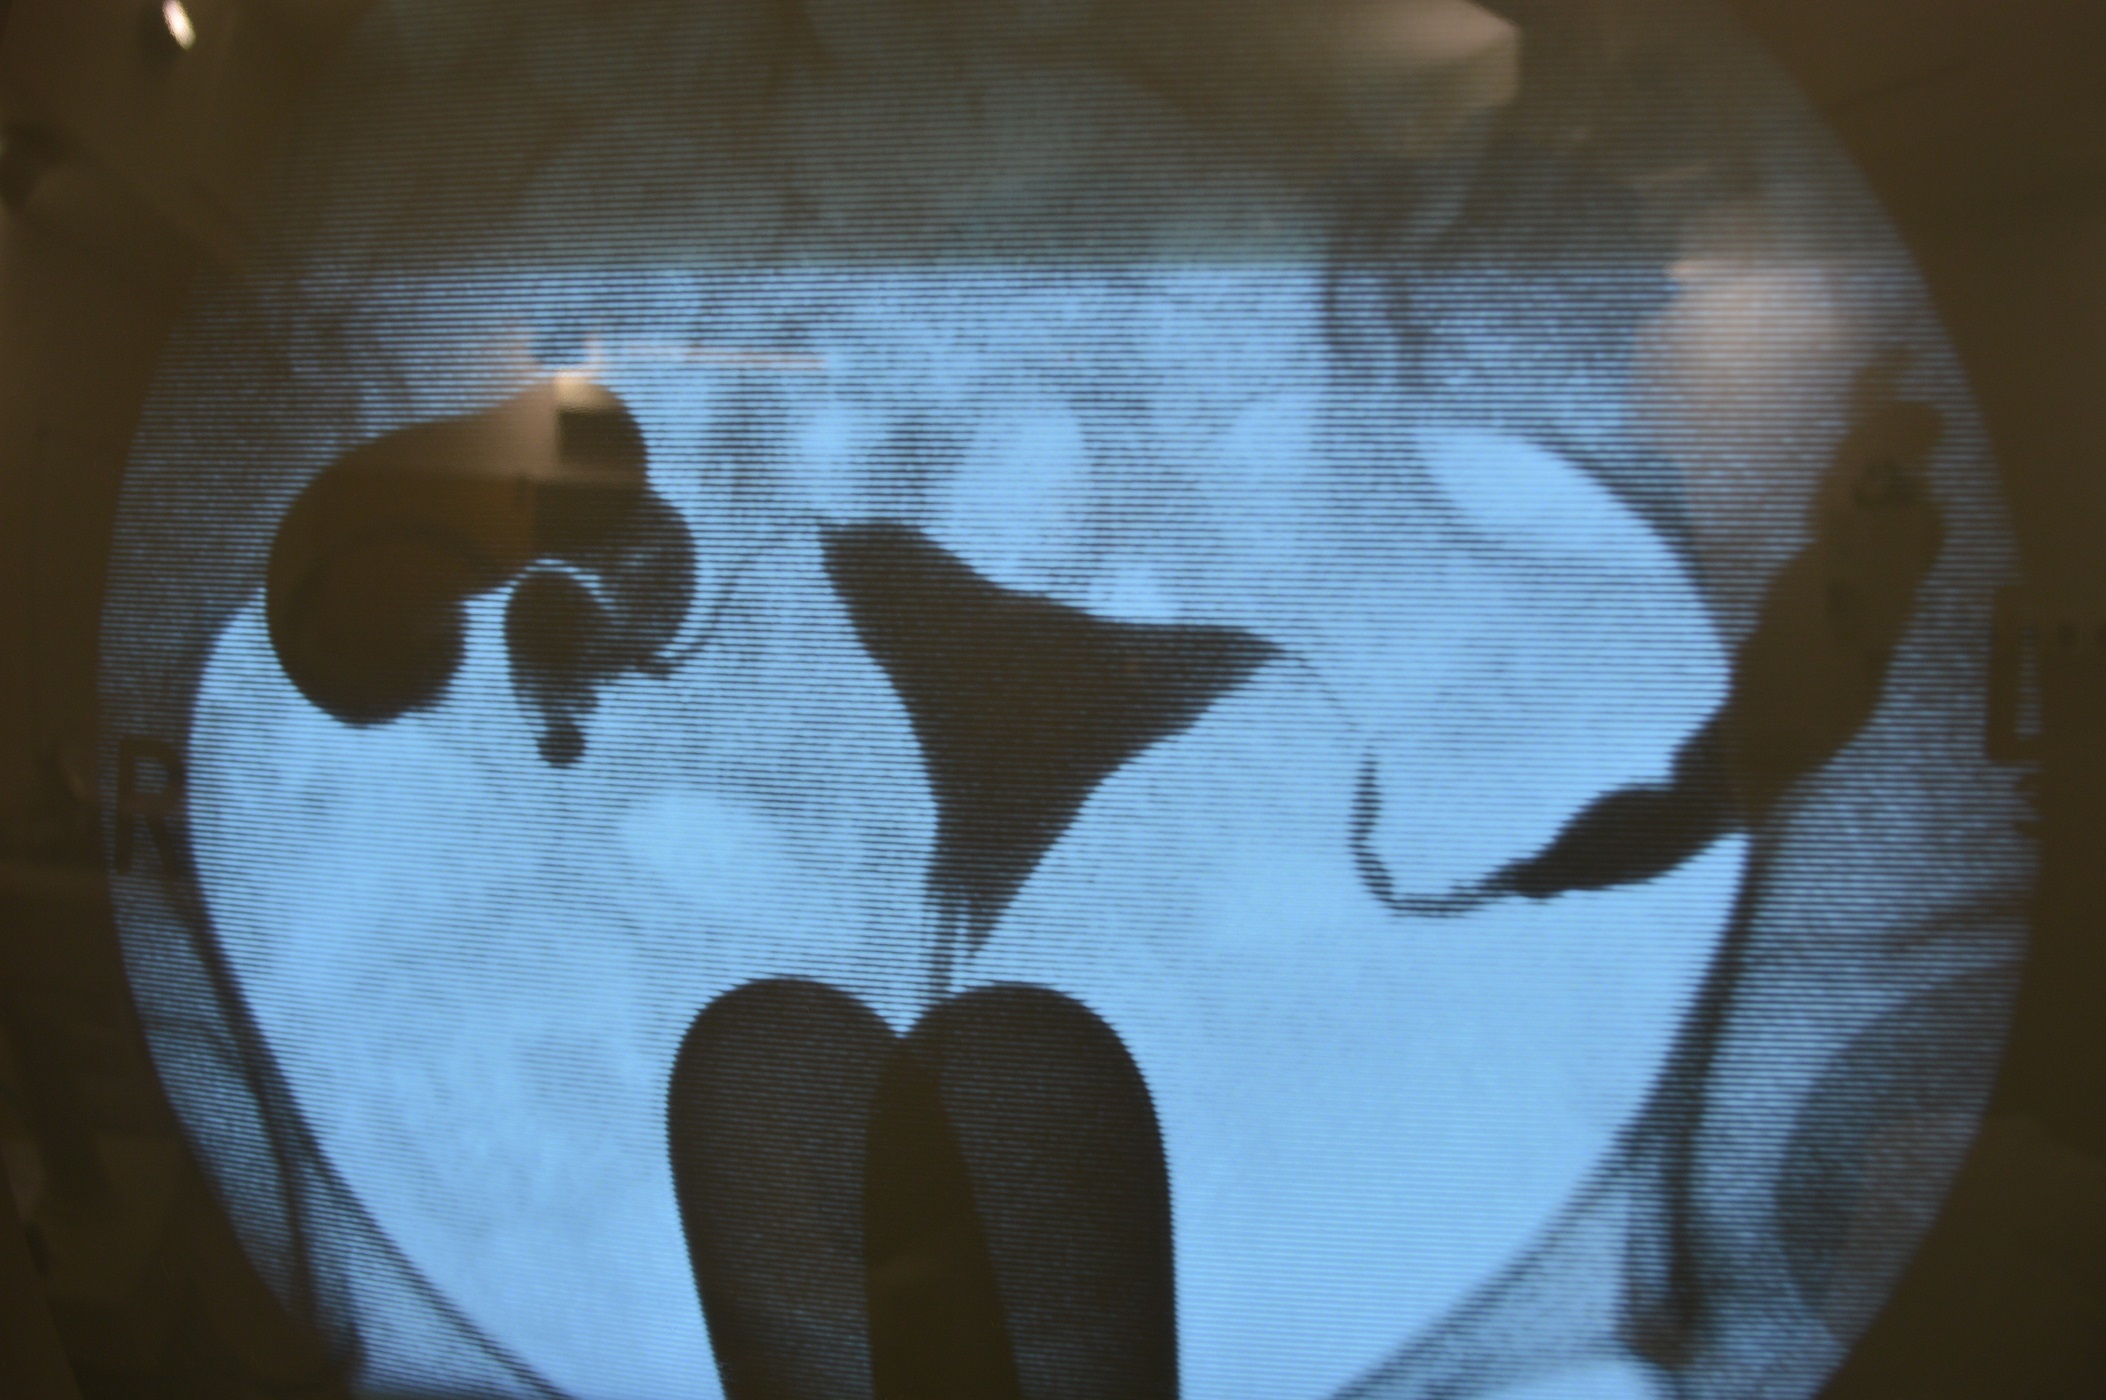

Медицинские снимки: Проходимость маточных труб